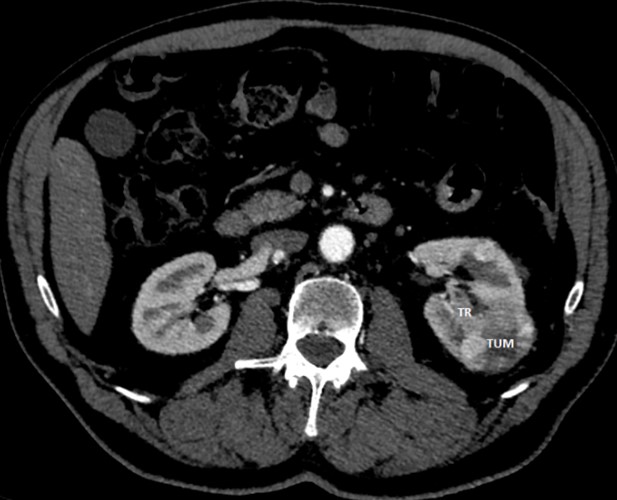

Examination: MSCT - left kidney two tumors, segmental renal vein tumor thrombosis (Fig. 5); gastroscopy - an ulcer of the stomach cardial part (biopsy: fragments of adenocarcinoma of a tubular and cribriform structure with superficial foci) (Figure 6).

Figure 6: MSCT, left kidney cancer (TUM) with segmental renal vein tumor thrombus (TR)